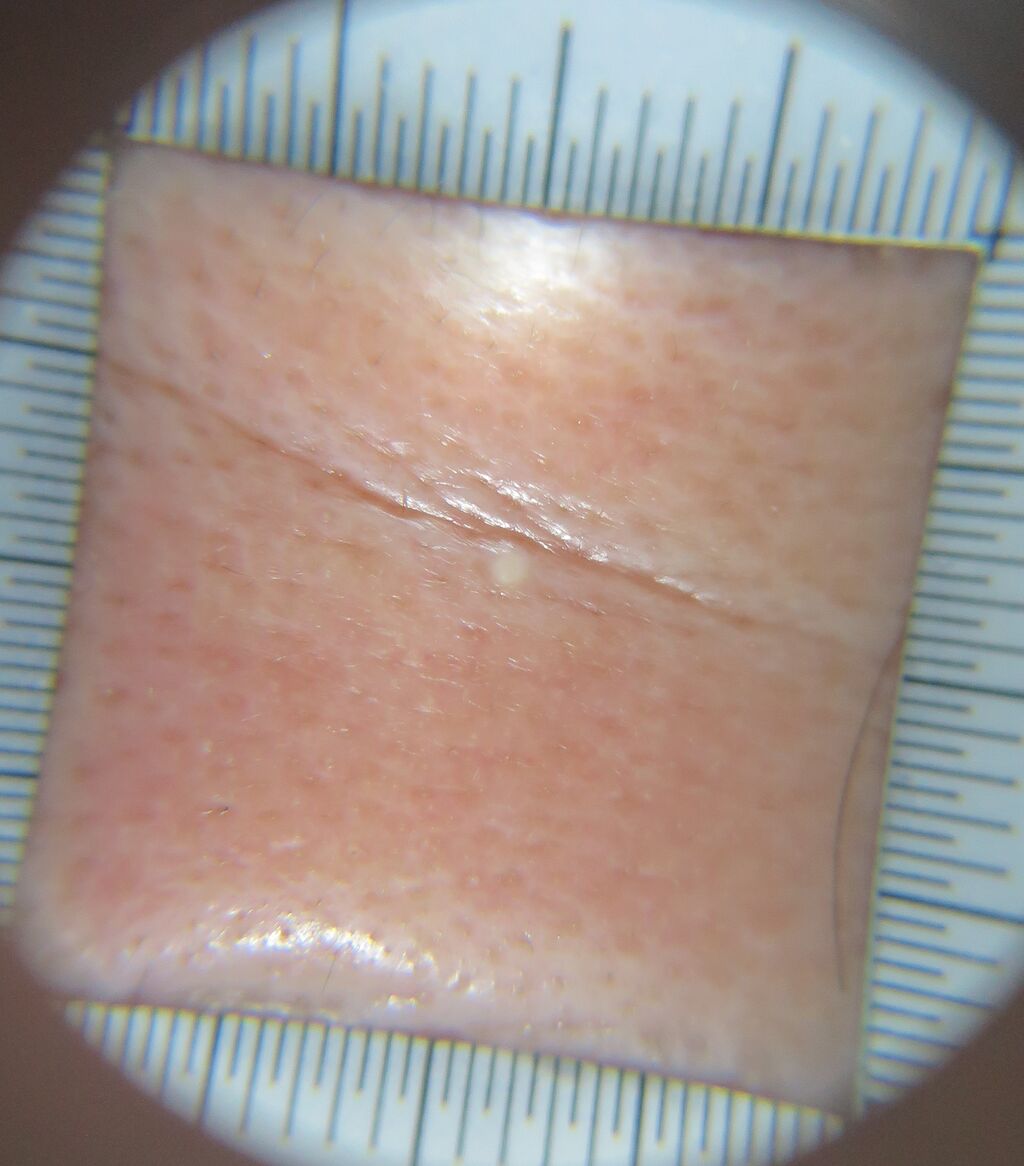

秋のおすすめ治療では、

脚全体の脱毛(太もも、ひざ、ひざ下)を39800円(税込み)で施術しています。